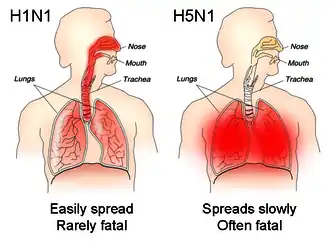

Uma parte do processo que permite aos vírus da gripe invadir as células é a clivagem da proteína viral hemaglutinina por qualquer uma das diferentes proteases humanas.[57] Nos vírus de baixa patogenicidade, a estrutura da hemaglutinina implica que só possa ser clivada por proteases que se encontrem na garganta e nos pulmões, pelo que estes vírus não são capazes de infetar outros tecidos. No entanto, em estirpes bastante virulentas, como o H5N1, a hemaglutinina pode ser clivada por uma ampla gama de proteases, permitindo ao vírus disseminar-se por todo o corpo.[76]

A proteína viral hemaglutinina é responsável por determinar não só que espécies é que determinada estirpe pode infetar, mas também em que local do trato respiratório é que essa estirpe se irá alojar.[77] As estirpes que são facilmente transmitidas entre pessoas possuem proteínas de hemaglutinina que se ligam a receptores na parte superior do trato respiratório, como os do nariz, garganta e boca. Por outro lado, a estirpe potencialmente mortal de H5N1 liga-se a recetores profundos dos pulmões.[78] Esta diferença no local de infeção pode explicar porque é que o H5N1 causa pneumonia viral grave nos pulmões, ao mesmo tempo que não é facilmente transmitida pela tosse ou por espirros.[79][80]